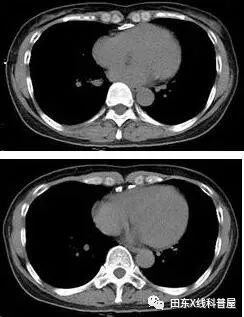

患者女,64岁,发作性心悸入院

急诊心电图:室上性心动过速,异常Q波,T波异常,右心室肥厚,心率111次/分

CASE 3

患者女,48岁,反复心悸、胸闷,曾行心脏检查无异常(具体不详)